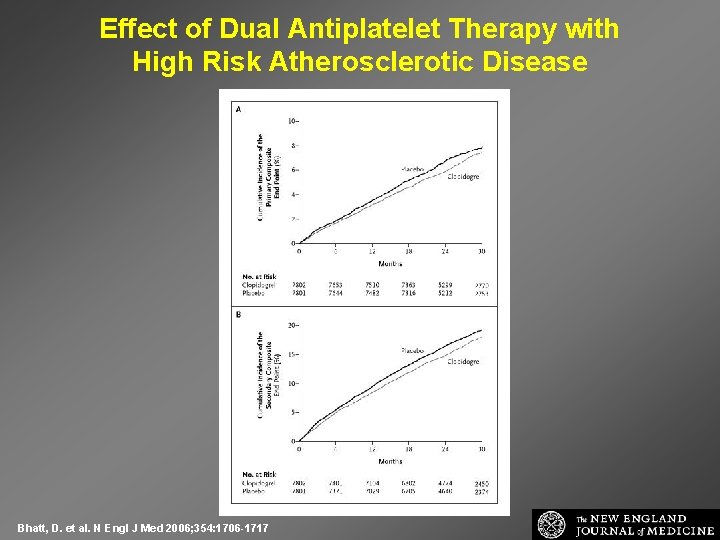

Effect of Dual Antiplatelet Therapy with High Risk Atherosclerotic Disease Bhatt, D. et al. N Engl J Med 2006; 354: 1706 -1717